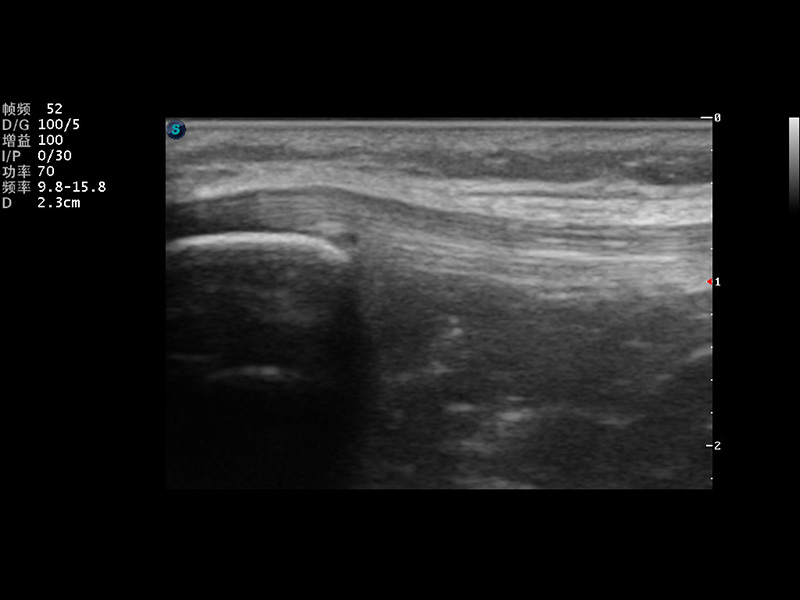

S9便携式彩色多普勒超声诊断仪是竞技宝(JJB)官方网站研发的高端便携彩超设备,外观设计新颖、产品性能卓越。S9在便携超声领域采用了突破传统的触摸屏交互设计,并以先进的软件硬件技术和设计理念,为您带来清晰的图像质量、稳定的工作性能和便捷的操作体验。

μ-Scan微米成像